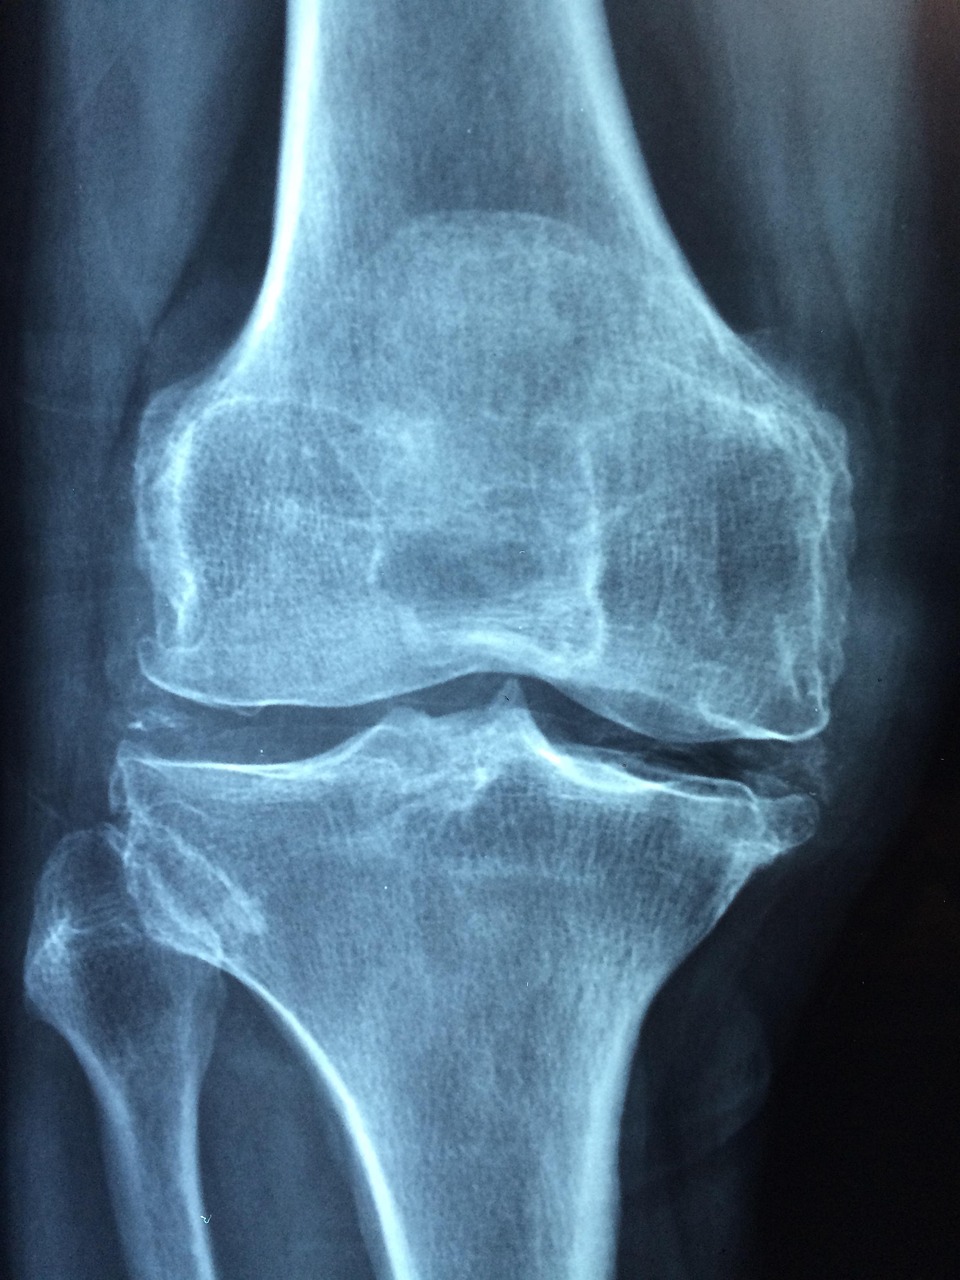

Kniearthrose: Die häufigste und am besten erforschte Form

Die Kniearthrose,medizinisch als Gonarthrose bezeichnet, ist die am häufigsten diagnostizierte Form. Besonders ältere Menschen leiden aufgrund einer Kombination aus altersbedingtem Knorpelverschleiß und Begünstigung durch Übergewicht an diesem Gelenkverschleiß. Doch auch Verletzungen, wie etwa Meniskusschäden oder Bänderrisse, erhöhen die Gefahr erheblich.

Typische Beschwerden sind belastungsabhängige Schmerzen, die zunächst nach Belastung und im weiteren Verlauf auch in Ruhephasen auftreten können. Die Beweglichkeit des Knies nimmt allmählich ab, und es können Schwellungen durch entzündliche Prozesse entstehen. Bestehendes Übergewicht steigert die Belastung zusätzlich.